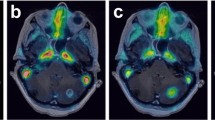

18F-Fluorocholine PET/CT images together with tumor time-activity curves and surgical samples are shown for two representative patients with (Fig. 4) and without (Fig. 5) pathologic confirmation of tumor recurrence, illustrating different 18F-Fluorocholine pharmacokinetics between lesions.

18F-Fluorocholine PET for a lung cancer patient with pathological confirmation of recurrent tumor. (A) Axial view of the last dynamic PET frame (10-min acquisition time, 30–40-min post-injection), fused with corresponding CT, showing the 11-cm3 metastatic lung adenocarcinoma in superior-anterior left frontal resection cavity with PET-derived SUVmax of 10.1. Post-Gadolinium contrast T1-weighted MRI and 18F-FDG PET are included for comparison. Color bar scales are in units of SUVbw. (B) Photomicrograph on the left panel shows metastatic carcinoma with focus of necrosis at upper right. Hematoxylin-eosin, 40x magnification. Right panel shows Ki-67 staining with a proliferative index of 90%. In total, 12 surgical samples were analyzed for this patient. All of them indicated recurrent tumor and the presence of necrosis. Highest SUVmax was 13.1. (C) Time-activity curve for intratumor area of highest 18F-Fluorocholine uptake (red). SUV, vB, K1, k2, k3, and KiP were 8.8, 0.04, 1.27 mL/min/g, 0.18 min−1, 0.17 min−1, and 0.81 mL/min/g, respectively. Corresponding values for normal brain tissue were 0.2, 0.06, 0.02 mL/min/g, 0.13 min−1, 0.13 min−1, and 0.01 mL/min/g, respectively (TAC showed in blue). Unmetabolized and metabolized 18F-Fluorocholine in plasma are shown as solid and dashed gray lines, respectively. (D) Insert from panel (C), highlighting the normal brain uptake and 18F-Fluorocholine activity in plasma

18F-Fluorocholine PET for a lung cancer patient with no recurrent tumor seen in the surgical samples. (A) Axial view of the last dynamic PET frame (10-min acquisition time, 30–40-min post-injection), fused with corresponding CT, showing the 1.4 cm3 lesion in paramedian right parietal lobe that was suspicious for viable tumor. PET-derived SUVmax was 1.7. Post-Gadolinium contrast T1-weighted MRI and 18F-FDG PET are shown for comparison. (B) The left half of the photomicrograph exhibits necrotic neuroparenchyma with fibrinous exudates. Seen in the right half are a few reactive lymphocytes and siderophages. Hematoxylin-eosin, 40x magnification. In total, 12 samples were analyzed for this patient. None of them indicated recurrent tumor, whereas necrosis was detectable in 7 out of 12 tissue samples. No evidence of proliferation was noted. Highest SUVmax derived from samples was 4.0. (C) Time-activity curve for intratumor area of highest 18F-Fluorocholine uptake (red). SUV, vB, K1, k2, k3, and KiP were 1.7, 0.06, 0.23 mL/min/g, 0.11 min−1, 0.14 min−1, and 0.13 mL/min/g, respectively. Corresponding values for normal brain tissue were 0.1, 0.07, 0.02 mL/min/g, 0.23 min−1, 0.17 min−1, and 0.01 mL/min/g, respectively (TAC shown in blue). Unmetabolized and metabolized 18F-Fluorocholine in plasma are shown as solid and dashed gray lines, respectively. (D) Insert from panel (C), highlighting the normal brain uptake and 18F-Fluorocholine activity in plasma